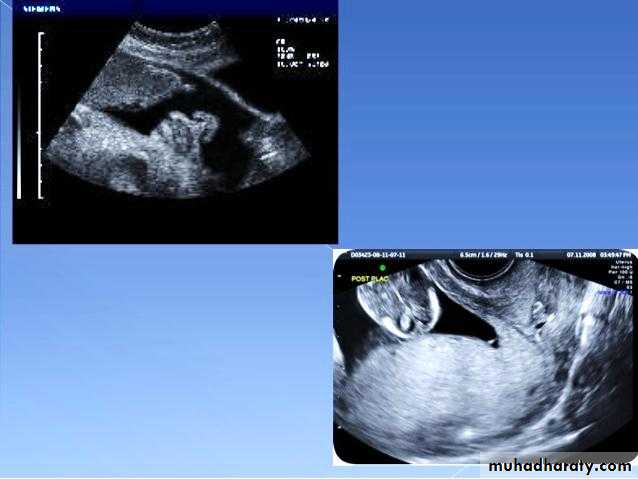

Ectopic pregnancy refers to the implantation of a fertilised ovum outside of the uterine cavity.

The ultrasound exam should be performed both transabdominally and transvaginally. The transabdominal component provides a wider overview of the abdomen, whereas a transvaginal scan is important for diagnostic sensitivity.

Positive sonographic findings include:

empty uterine cavity or no evidence of intrauterine pregnancy

Pseudo gestational sac or decidual cyst: may be seen in 10-20% of ectopic pregnancies

Direct visualization of the sac at the adenxia .